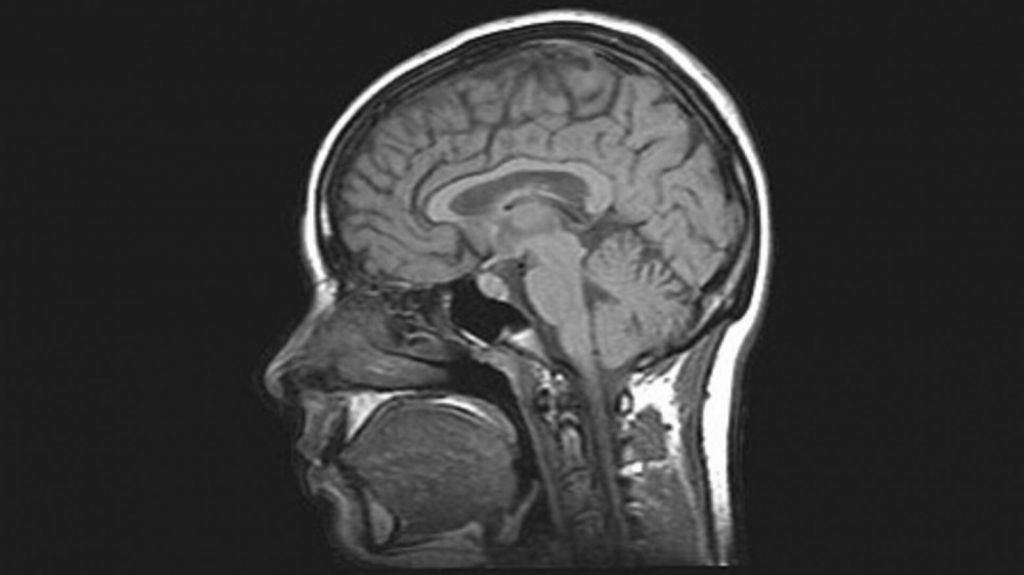

Η απότομη αύξηση της πίεσης του αίματος με κάθε καρδιακό παλμό αναγκάζει τον εγκέφαλο να πάλλεται αιωρούμενος μέσα στο εγκεφαλονωτιαίο υγρό.

Μια νέα παραλλαγή της μαγνητικής τομογραφίας, ικανή να παρακολουθεί τους ιστούς σε τρεις διαστάσεις και σε πραγματικό χρόνο, αποκαλύπτει πώς ο εγκέφαλος πηγαινοέρχεται μέσα στο κρανίο με κάθε σφυγμό.

Η απότομη αύξηση της πίεσης του αίματος με κάθε καρδιακό παλμό αναγκάζει τον εγκέφαλο να πάλλεται αιωρούμενος μέσα στο εγκεφαλονωτιαίο υγρό που προστατεύει το κεντρικό νευρικό σύστημα.

YouTube thumbnail

Τα βίντεο που παρουσίασαν ερευνητές στις ΗΠΑ παρουσιάζουν τις κινήσεις του εγκεφάλου πιο έντονες από ό,τι πραγματικά είναι ώστε να γίνονται καλύτερα ορατές. Στην πραγματικότητα, η μετατόπιση κυμαίνεται από τα 0,05 έως τα 0,4 χιλιοστά, αναφέρουν οι ερευνητές σε ανακοίνωσή τους.

Η νέα μέθοδος ονομάστηκε «ενισχυμένη μαγνητική τομογραφία τριών διαστάσεων (3D aMRI) ακριβώς επειδή «ενισχύει», ή μεγεθύνει, τις κινήσεις των ιστών.

Η κλαστική μαγνητική τομογραφία δίνει εικόνες δύο διαστάσεων, ωστόσο η ερευνητική ομάδα στο Πανεπιστήμιο Στάνφορντ, την Κλινική «Όρος Σινάι» και άλλα αμερικανικά ιδρύματα μπόρεσε να συνδυάσει αλλεπάλληλες λήψεις, τραβηγμένες από διαφορετική οπτική γωνία, για να δημιουργήσουν βίντεο τριών διαστάσεων.